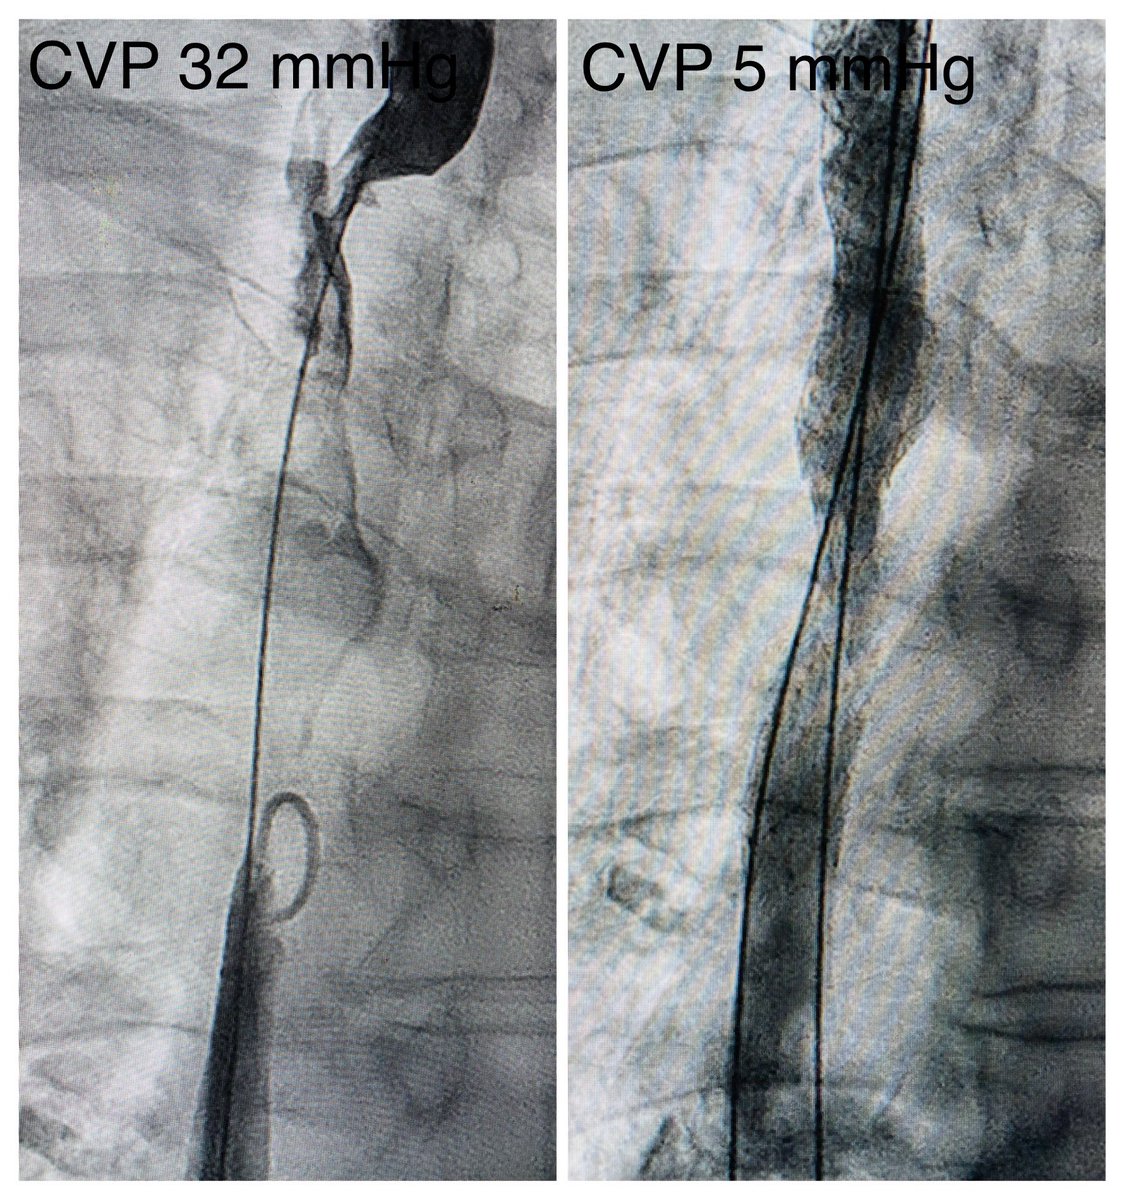

Mediastinal mass. SVC syndrome. L7 thrombectomy. 16x140 ZV stent. Immediate resolution of head and neck venous congestion.